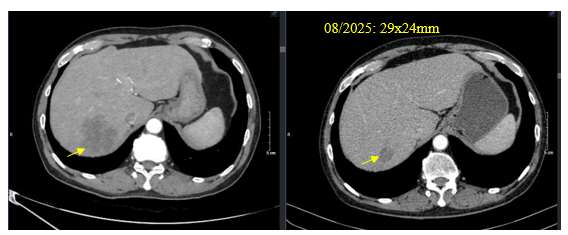

Chụp cắt lớp vi tính bụng: Tổn thương gan phải giảm kích thước: 45x47mm

Hình 2. Hình ảnh khối nhu mô gan phải – tổn thương di căn